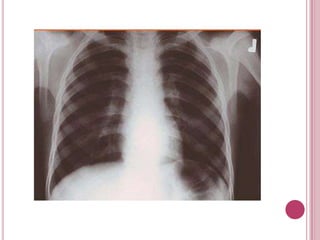

RADIOGRAFIA DE TORAX

Es usada para definir anormalidades de los

pulmones como fluido excesivo alrededor de los

pulmones, neumonía, bronquitis, asma, quistes o

cáncer.

 También se pueden visualizar determinadas

estructuras óseas del tórax, huesos rotos o

anormalidades de los huesos de la espina dorsal

en el tórax.

RADIOGRAFIA DE TORAX Esusada para definir anormalidades de los pulmones como fluido excesivo alrededor de los pulmones, neumonía, bronquitis, asma, quistes o cáncer.  También se pueden visualizar determinadas estructuras óseas del tórax, huesos rotos o anormalidades de los huesos de la espina dorsal en el tórax. 